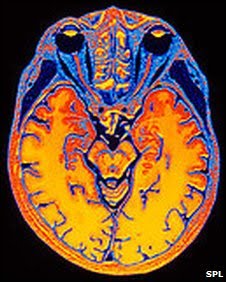

La gente que pasa más tiempo adquiriendo una educación parece estar más protegida de los efectos de la demencia en el cerebro, revela un estudio.

Un equipo de científicos del Reino Unido y Finlandia descubrió que los signos de la demencia en el cerebro aparecen tanto en personas con más educación como aquéllas con menos educación.

En esta investigación los científicos examinaron en autopsias los cerebros de 872 personas que habían participado en tres grandes estudios sobre envejecimiento.

Los investigadores encontraron que las personas con mejor educación estaban mejor capacitadas para compensar los efectos del trastorno.

También descubrieron que por cada año que el individuo pasó educándose, había 11% menos riesgo de desarrollar la enfermedad.